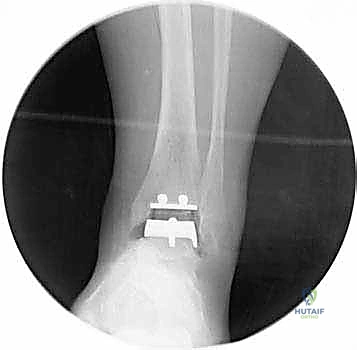

تعتمد دقة الجراحة على المحاذاة الصحيحة. يتم استخدام أجهزة توجيه متطورة (Jigs) تثبت على عظمة الساق باستخدام دبابيس معدنية. يتم التحقق من صحة الزوايا والمحاور باستخدام جهاز الأشعة السينية المباشر داخل غرفة العمليات (C-arm Fluoroscopy). يضمن الدكتور هطيف أن يكون القطع موازياً للأرض تماماً عند وقوف المريض.

5. القطع العظمي الظنبوبي (Tibial Bone Cut)

باستخدام منشار جراحي دقيق التذبذب، يتم إزالة شريحة رقيقة جداً (بضعة مليمترات) من السطح السفلي التالف لعظمة الظنبوب. يتم القطع بحذر شديد لتجنب إصابة الأوتار الخلفية أو الأوعية الدموية.